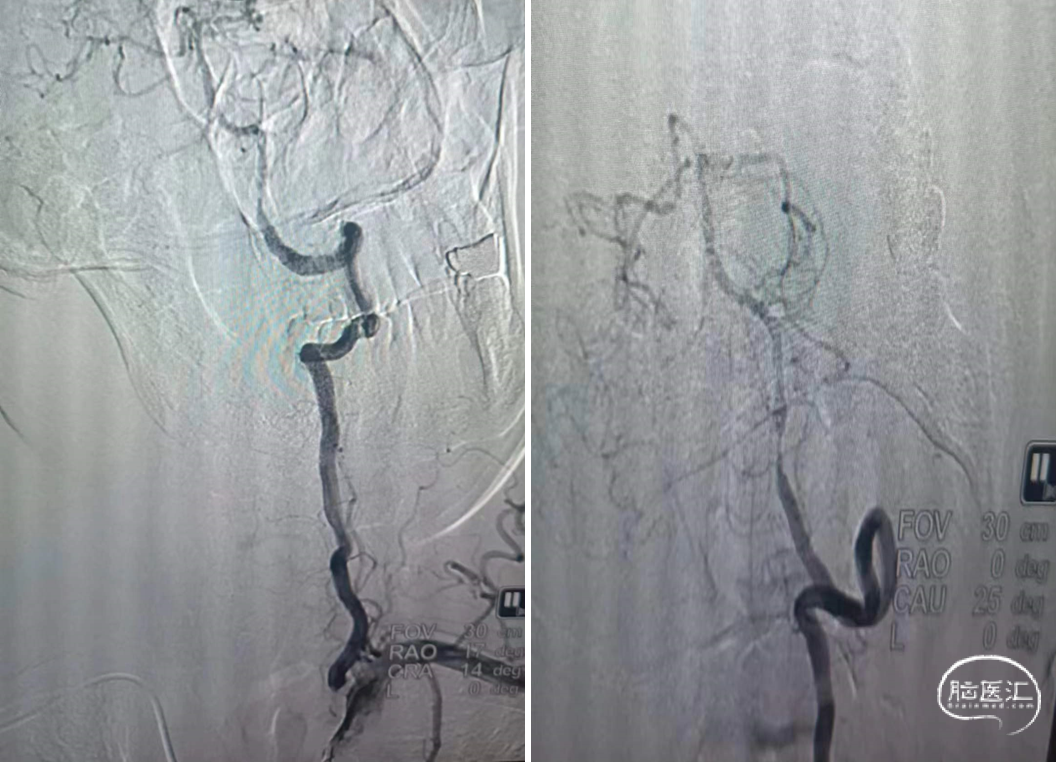

Tethys®中间导引导管沿导丝顺利到达病变近端附近,锁骨下至椎动脉转弯处充分体现了近端良好的⽀撑性与抗折性,帮助后续⾎管开通治疗建⽴稳定通路系统

中间导管到位后造影

微导丝通过狭窄段

微导丝置于左侧大脑后

球囊到位

3mm*20mm球囊扩张

复查造影

5min后复查造影